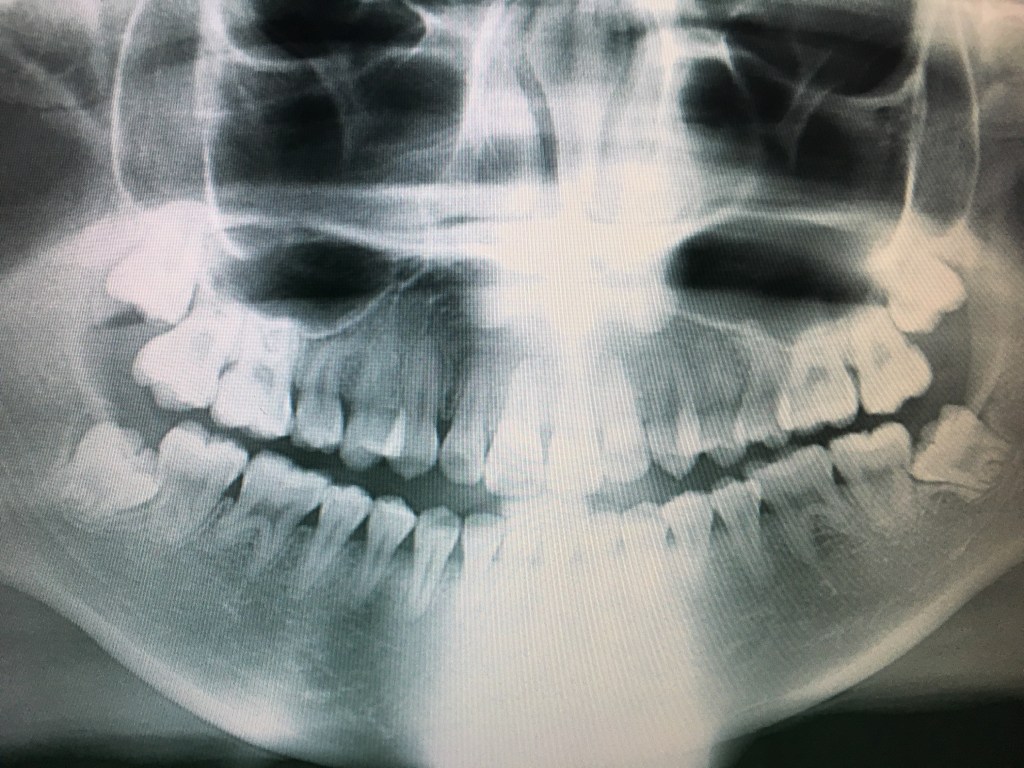

Mursu nussi kalastajaa suuhun ja rikkoi laiturin Kotkassa – katso kalastajan leukaröntgenkuvat! Mursu on nussinut kalastajaa suuhun. Lähde: Kalastajan kotialbumi Jaa: Share on Telegram(Avautuu uudessa ikkunassa) Telegram Share on WhatsApp(Avautuu uudessa ikkunassa) WhatsApp Tykkää Lataa... Jätä kommentti Peruuta vastaus Δ